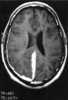

Tuberculosis of meninges

Tuberculous meningitis is also known as TB meningitis or tubercular meningitis. Tuberculous meningitis is Mycobacterium tuberculosis infection of the meninges—the system of membranes which envelop the central nervous system. [Source: Wikipedia ]